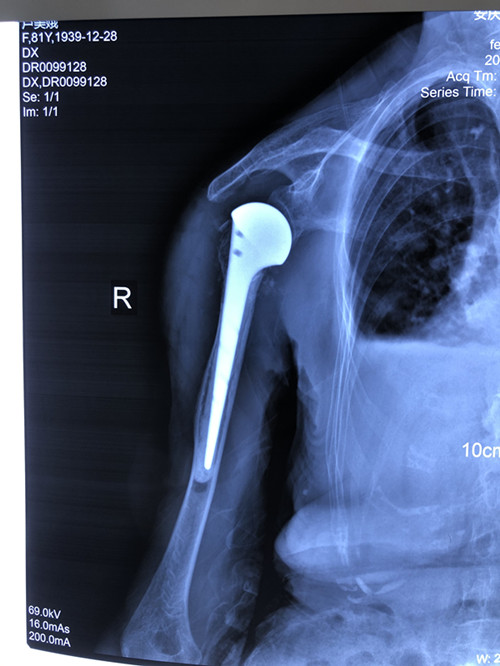

人工肱骨頭置換術(shù)是一個(gè)“精細(xì)活”,技術(shù)要求高、操作難度大,人工假體尺寸的選擇、安放的位置都很有講究。手術(shù)當(dāng)天,張明龍主任帶領(lǐng)團(tuán)隊(duì)僅用時(shí)一個(gè)多小時(shí),就成功將“人工肩關(guān)節(jié)”植入患者體內(nèi)。

術(shù)后,李老太恢復(fù)良好,第3天就開(kāi)始進(jìn)行輕度被動(dòng)前屈、外展活動(dòng),一周后恢復(fù)擺動(dòng)、康復(fù)功能鍛煉。